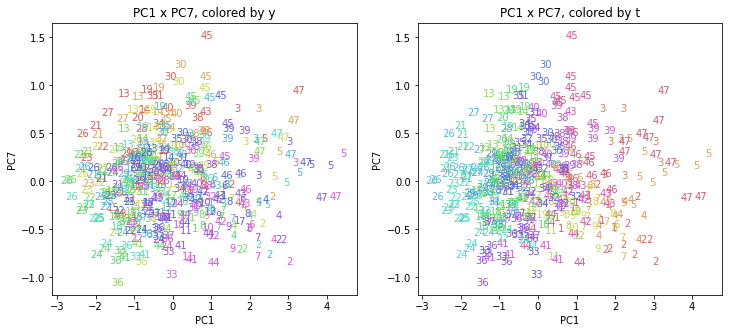

PCAの結果の第n主成分をPCnと表記します。

医療費データの場合と同様に、PCAの結果を見やすく表示するため、seabornのカラーパレットを使って、年月別、都道府県別に色分けして図示してみます(左側が年月別に色分け、右側が都道府県別に色分け)。PC1~PC8まで表示しました。

都道府県番号の表示

上の色分けだけでは都道府県が区別しにくいので、医療費データの場合と同様に、点の代わりに都道府県番号をプロットした図も描いておきます(色分けは上と同じ)。

医療費データの場合ほどはっきりとはしていませんが、PC2が概ね時間の経過を表す成分で、残りの成分が時点によって変わらない地域の特徴を表す成分となっているようです。

また、PC1×PC3を見ると、47沖縄が他の都道府県からかなり離れたところに位置しており、沖縄の地域差が際立っているのが分かります。これは、以前別の記事で年齢階級のない健診データでPCAを実行した場合と似た結果となっています。